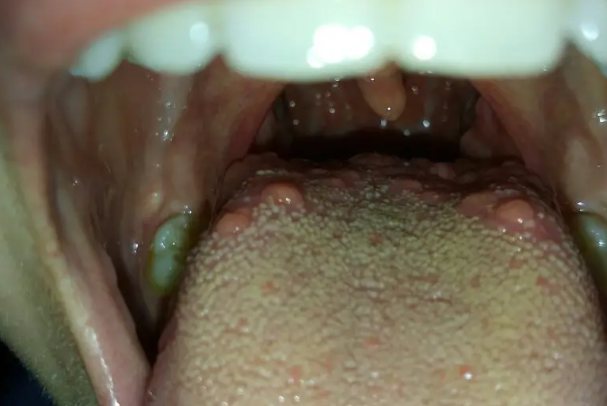

喉咙处有小疙瘩可能是轮廓乳头或舌乳头炎。

轮廓乳头是人体舌上的生理性结构,属于舌乳头的一种,有8~12个,较大,呈轮状,沿人字沟排列。乳头周围有深沟环绕,含有味蕾,以司味觉。

舌乳头炎发生在舌头根部,主要包括轮廓乳头炎和叶状乳头炎。轮廓乳头炎症时乳头红肿突起,表现为舌头靠近喉咙处有小疙瘩,疼痛不明显。

轮廓乳头为生理性组织,可能因体积较大,被误认为是肿瘤,通常无须治疗。舌乳头炎应去除局部刺激,避免吃辛辣刺激性食物,积极治疗系统性疾患,如有贫血、营养不良等明确病因者应给予纠正。